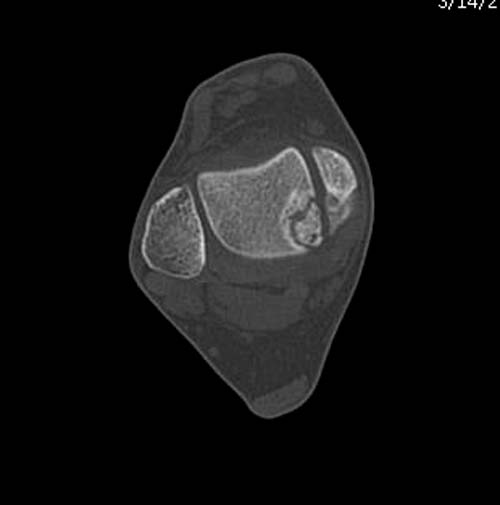

Разбираемый случай не имеет ничего общего с классическим Аваскулярным Некрозом Таранной кости. Здесь так назывемый (osteochondral defect) или osteochondritis dissecans (OCD) таранной кости, при котором патология локализуется в медиально-верхнем нагрузочном отделе. В основном OCD

встречается после хронической травмы, но бывают случаи врожденного генеза, которые обнаруживаются при случайных исследованиях.

Симптоматология  OCD выражается слабым отеком, а более сильные боли наступают после физической нагрузки. В отличие от АВН тарана, когда боли постоянные, а при OCD боли изчезают после отдыха. В начальных стадиях

на рентгенограммах не всегда заметны склерозные участки, и поэтому в большинстве диагноз устанавливается поздно. Приход КТ и МРТ улучшил диагностику, и в срезах внутри кисты можно увидеть жидкость, но это не означает проявление симптоматологии. Симптомы проявляются с момента образования внутрисуставных краевых фрагментаций!